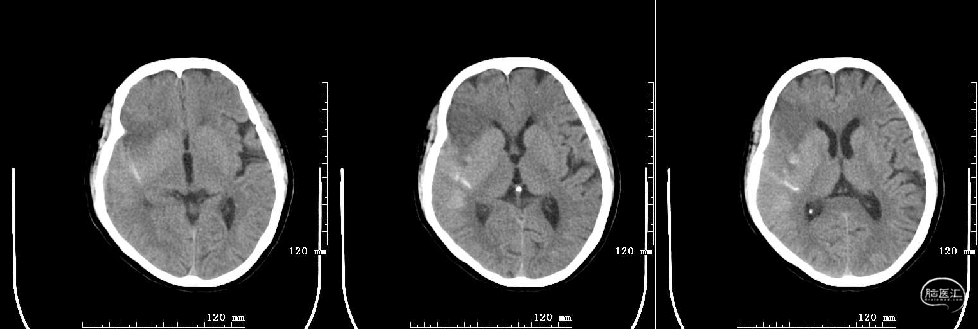

术后第二天:

术后第二天复查头颅MRI

4月2日(术后10天)患者左肢无力及言语障碍较前好转,语言流利,双眼未见凝视,伸舌居中,示齿口角稍右歪,左侧鼻唇沟稍浅,四肢肌力V级。NIHSS评分1分(面瘫1分),mRS 1分。

随访:2022年5月6日(术后45天)NIHSS评分0分mRS 0级。

随访:2022年10月11日(术后约6月)NIHSS评分0分mRS 0级。